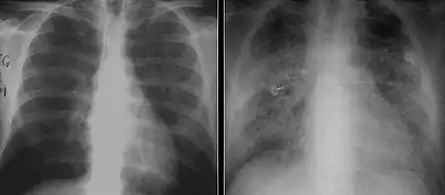

The diagnosis can be confirmed by the characteristic appearance of the chest X-ray and an arterial oxygen level (PaO2) that is strikingly lower than would be expected from symptoms. Gallium 67 scans are also useful in the diagnosis. They are abnormal in about 90% of cases and are often positive before the chest X-ray becomes abnormal. Chest X-ray typically shows widespread pulmonary infiltrates. CT scan may show pulmonary cysts (not to be confused with the cyst-forms of the pathogen).

These chest radiographs are of two patients. Both show ground glass opacities. The left X-ray shows a much more subtle ground-glass appearance while the right X-ray shows a much more gross ground-glass appearance mimicking pulmonary edema.[6]